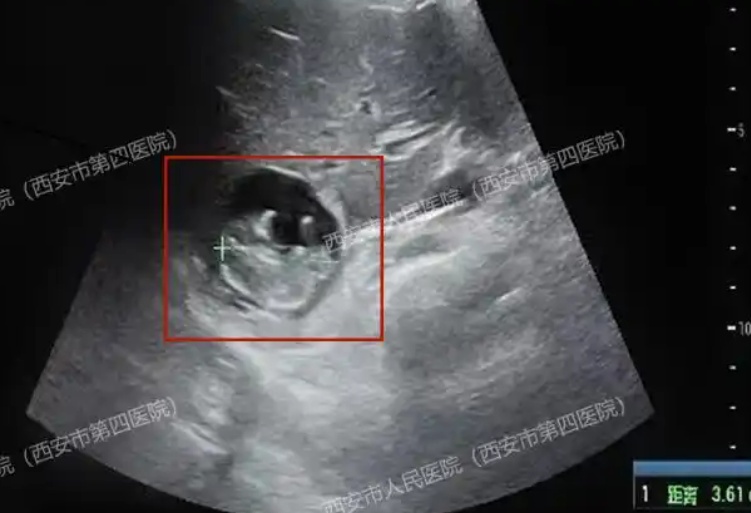

王女士(化名)40岁,在停经50天后,去西安市人民医院(西安市第四医院)检查。医生告诉她:经抽血检查,确诊怀孕。但王女士还来不及高兴,医生又说:在子宫及输卵管附近均未能找到孕囊。

“停!”超声医生的探头在患者的腹部停住......从空空如也的子宫向周边探寻,终于在肝脏的边缘,找到一个小生命!不仅胎心搏动强劲有力,胎盘雏形也已形成,测量的顶臀径约36mm,估算的孕周近11周了!

这种孕囊寄生于肝脏表面的情况,被称为“肝脏妊娠”,是一种极其特殊的宫外孕。据文献报道,原发性肝脏妊娠,发病率约为子宫妊娠的1:15000。目前可查的全球文献报道不超过50例!